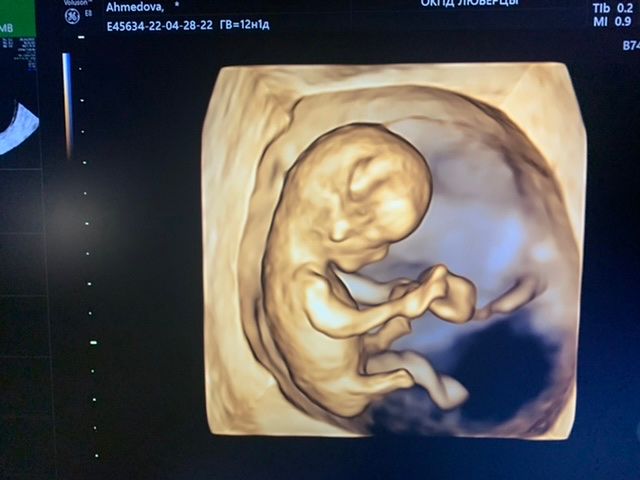

Здравствуйте подскажите какой пол у ребёнка? 12 недель

На таком сроке так пол не смотрят, не информативно ещё. А так чисто интуитивно по форме головы - мальчик)

Рано ещё судить) это может быть и клитор и половой член, но я за мальчика))(

Нужно смотреть в профиль, тут это будет пальцем в небо

Кажется что бугорок смотрит вверх, наверное мальчишка😊

Пока ещё ни кто точно не скажет ) половые органы не сформированы , но по фото сбоку я склоняюсь к девочке

На мальчика похож))

Не в этой проекции смотрят на ваших неделях) фото сбоку нужно )

Божечки, какой человечек в 12 недель) мне кажется девочка. Это вроде как нога в сгибе, а не писюшка.

Как думаете кто? Метод Рамзи